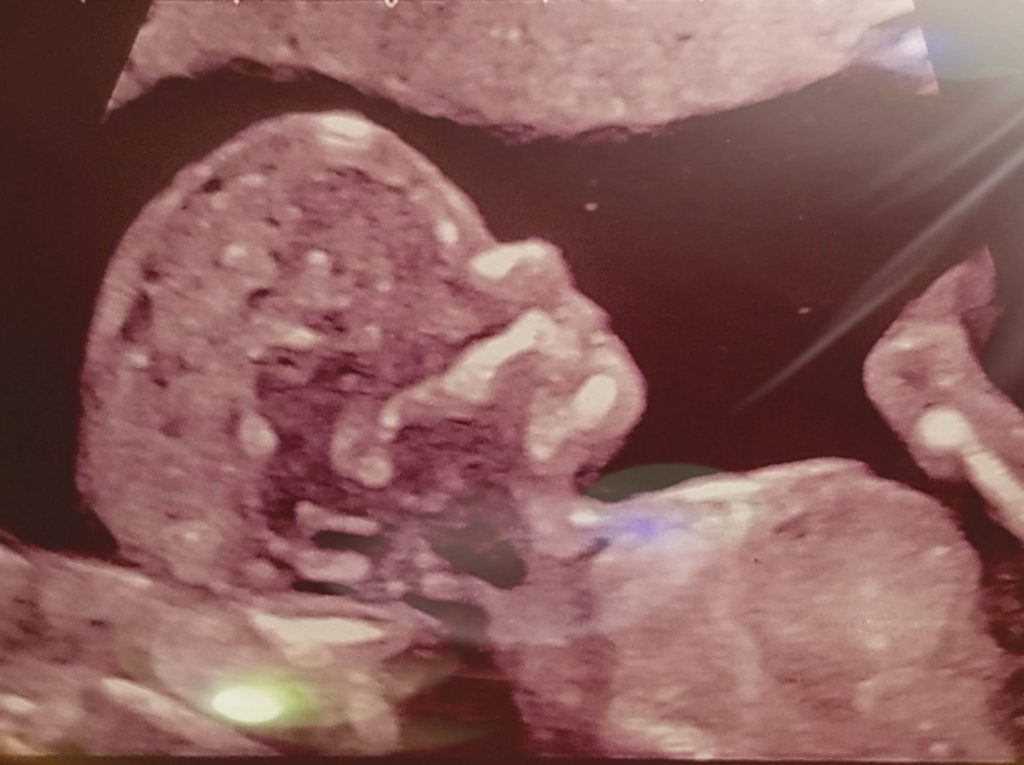

Gedichten Vanaf nu hebben mijn gedichten een nieuwe lay out! 30 weken Lynn Zo zonder jou… Geen straf zwaar genoeg#Peter R. de Vries Liefde op zijn best Vaderdag 2021 Waarom… Hartverwarmend Moederdag 2021 Lieve Lynn 02-05-2021 Van roze wolk naar felle brand Een klein geheimpje Teleurstellend Tussen hoop en vrees Kijk maar niet, onschuldig meisje#Coronarellen Onzichtbaar verdriet Op het strand Mama, het kleine meisje Knuffelkontje Als jij eens wist Een week geleden Dit delen: Delen op X (Opent in een nieuw venster) X Share op Facebook (Opent in een nieuw venster) Facebook Vind-ik-leuk Aan het laden...